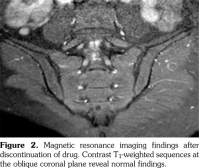

Physical examination revealed limited and painful lumbar movements in all directions. Modified Schober’s test was measured as 19 cm, while fingertip to floor distance was measured as 5 cm. There was full range of motion in hip joint, however, hip movements were painful. Chest expansion, sacroiliac provocation tests (mennel, gaenslen), and neurological examination findings were normal. Tinnel’s sign and Phalen’s maneuver were negative. Thus, the underlying origin of the back pain was considered to be inflammatory, and laboratory tests were performed. Laboratory analysis demonstrated normal biochemical values and complete blood count. Acute phase reactants including C-reactive protein and erythrocyte sedimentation rate were 3 mg/L (normal range: 0-3 mg/L) and 1 mm/h (0-15 mm/h), respectively. Urinalysis was normal. Serum vitamin B 12 and folic acid levels, thyroid function tests, and parathyroid hormone levels were within normal range. Hepatitis panel, including hepatitis B surface antigens, hepatitis B surface antibodies, hepatitis C virus antibodies, and human immunodeficiency virus antibodies, was negative. Serological evaluations including anti-cyclic citrullinated peptide and anti-nuclear antibody tests were negative. In addition, rheumatoid factor test was also negative. Spinal magnetic resonance imaging (MRI) was considered to be normal. However, sacroiliac MRI showed bilateral bone marrow edema and subchondral sclerosis (Figure 1 and Figure 2). Nerve conduction studies and electromyography revealed sensorimotor demyelinating polyneuropathy (Table 1 and Table 2).

In our case, clinical findings of neuropathy exacerbated after increasing the isotretinoin dose from 20 mg/day to 40 mg/day. Electrophysiological evaluation at sixth month revealed demyelinating polyneuropathy, being more prominent in sensorial fibers. Electrophysiological findings were normalized two months after withdrawal from treatment. These results are in agreement with other studies which detected neuropathy.(3,6)

Acne fulminans is a component of SAPHO syndrome (acronym for Synovitis, Acne, Pustulosis, Hyperostosis and Osteitis). In SAPHO syndrome, constitutional symptoms, abnormal laboratory findings and musculoskeletal symptoms are observed as well as necrotizing acne. Sacroiliitis was detected in 21% of the patients having acne fulminans in association with arthritis. In addition, development of sacroiliitis after systemic isotretinoin treatment was also reported in patients with SAPHO syndrome.(15,16) Dinçer et al.(17) reported sacroiliitis development in three patients aged 18-25 years who used 15-25 mg/day isotretinoin for a time period ranging from three months to two years. Unilateral sacroiliitis developed in patients who used isotretinoin for three months while bilateral sacroiliitis developed in patients who used isotretinoin for two years. Human leukocyte antigen B27 (HLA-B27) positivity was detected in one of three cases. Ekşioğlu et al.(3) also reported bilateral sacroiliitis and demyelinating polyneuropathy in a patient 20 years old, who used isotretinoin for three months (30 mg/day during first two months and 40 mg/day during last month). HLA-B27 positivity was detected in this case. Our patient was 25 years old and used isotretinoin for six months (20 mg/day during first three months and 40 mg/ day during last three months). Sacroiliitis developed bilaterally in our case. Sacroiliitis in our case was linked to isotretinoin use, as the patient had no musculoskeletal complaint prior to isotretinoin use. Furthermore, hip pain, back pain and active sacroiliitis findings on MRI emerged three months after prescription of isotretinoin. Complaints and active sacroiliitis findings on MRI disappeared two months after withdrawal from drug.